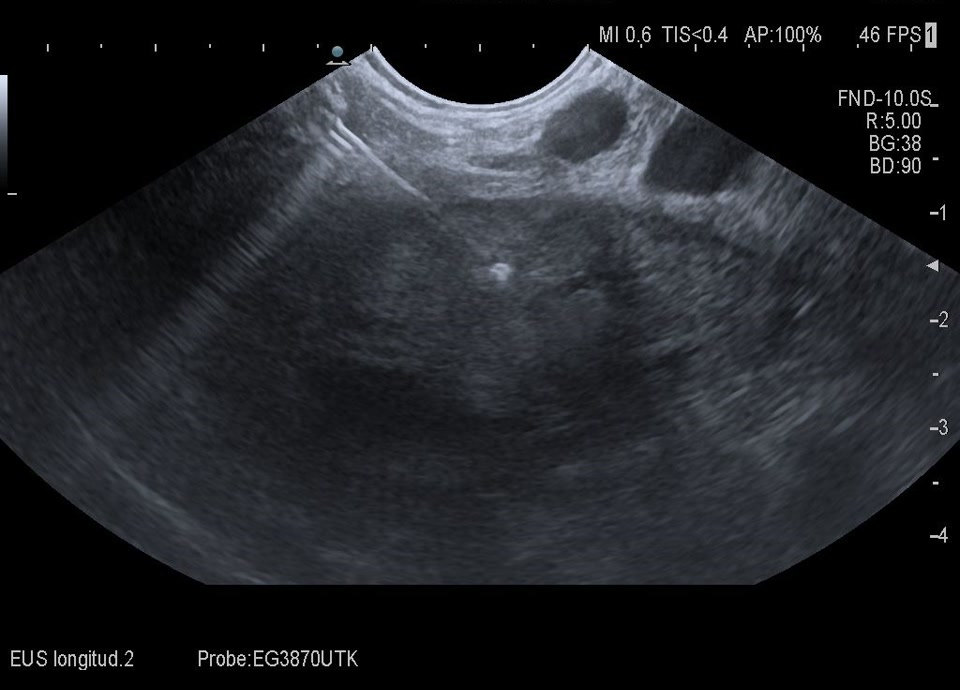

47-year-old patient presents to the emergency department with flank pain. Ultrasound shows a large, inhomogeneous, sharply defined mass in the left adrenal gland. A blood sample (including metanephrines) and a puncture (endosonographic access) are initiated for further clarification. Histologically adrenal cancer